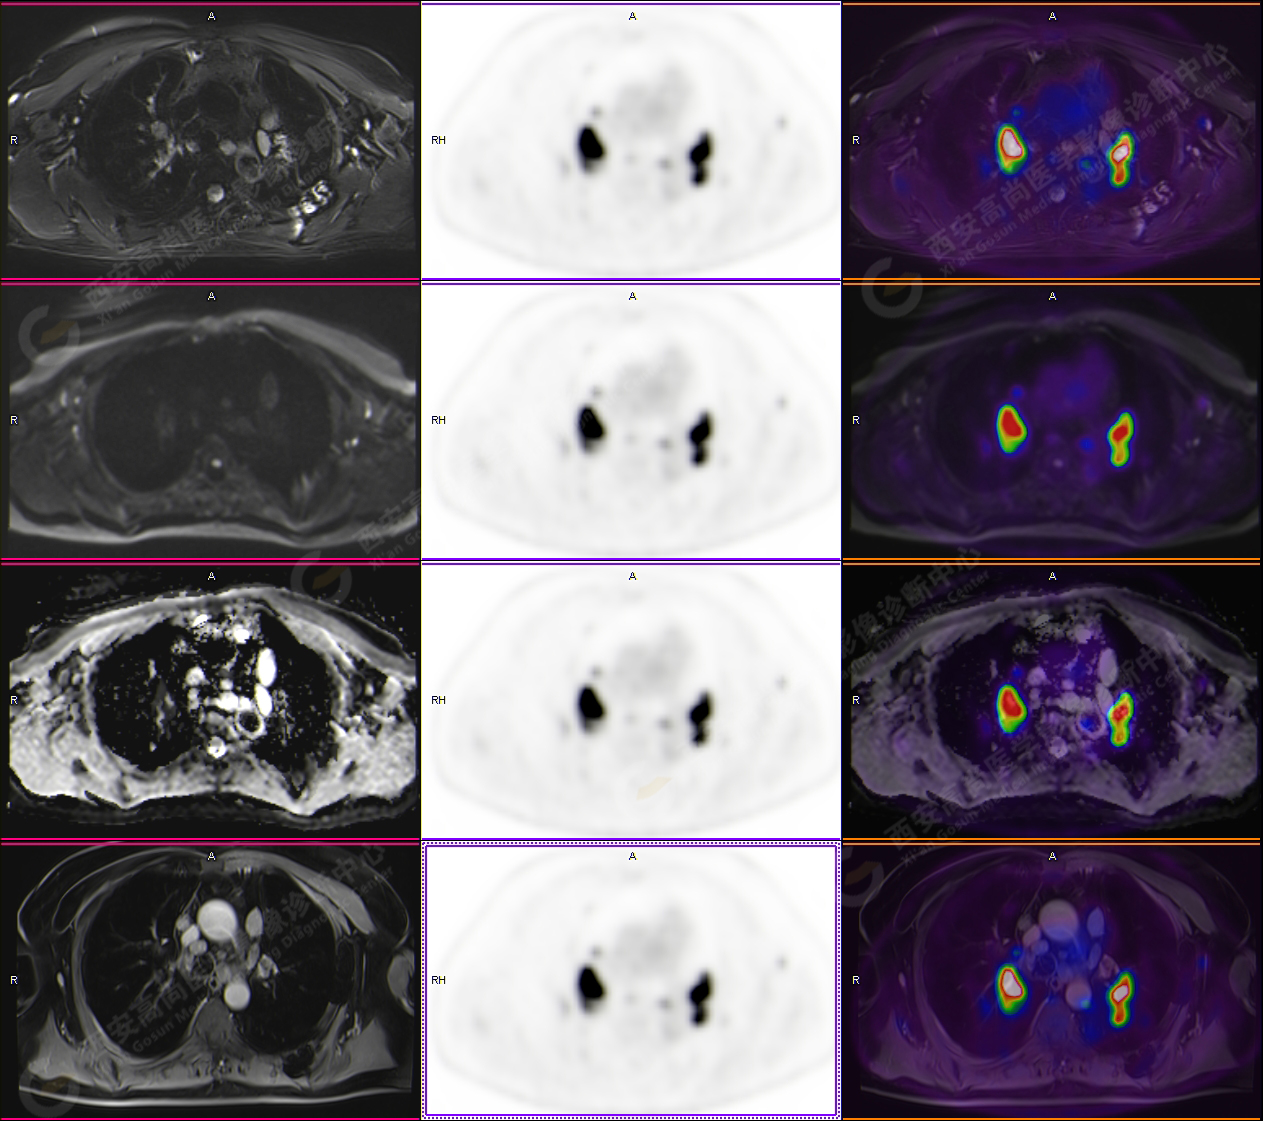

PET-MR圖像